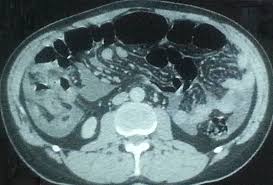

Malignant peritoneal mesothelioma (mpm) is an aggressive neoplasm that arises from the lining mesothelial cells of the peritoneum and spreads extensively within the confines of the abdominal cavity. Many of these signs and symptoms can be associated. Well differentiated papillary mesothelioma is characterized with a single layer of bland cuboidal cells lining fibrovascular cores, as demonstrated in this image. 13,28 malignant mesotheliomas of the peritoneum or pleura are rare tumors portending a poor prognosis. Home peritoneum peritoneum, omentum & mesentery mesothelioma. Additionally, omental mesothelioma is a rare type of mesothelioma that forms in the omentum, a part of the peritoneum that connects the stomach with other abdominal organs. Cystic epithelial neoplasms of the ovaries. A clinicopathologic study of 26 cases.

The tumor cells are strikingly similar to normal squamous. This type of cancer affects the lining that protects the contents of the abdomen and which also provides a lubricating fluid to enable the organs to move and. Cystic mesothelioma of the peritoneum. Approximately 35% of all mesotheliomas arise only from the peritoneum. A clinicopathologic study of 22 cases. Peritoneal mesothelioma is the name given to the cancer that attacks the lining of the abdomen. From there, they spread within the respective cavity and. Peritoneal mesothelioma is a cancer found in a thin membrane surrounding the abdomen known as the peritoneum. The majority of previously reported cases developed in the peritoneum of young women without a history of asbestos exposure. Adenocarcinoma) thus panel of immunohistochemical markers is generally required. A clinicopathologic study of 26 cases. Malignant peritoneal mesothelioma is the second most common form of mesothelioma and occurs in the tissue that lines the abdominal cavity and organs.1 the symptoms include pain and abdominal distention from ascites. Peritoneal mesothelioma affects the lining of the abdominal organs.

Malignant peritoneal mesothelioma is the second most common form of mesothelioma and occurs in the tissue that lines the abdominal cavity and organs.1 the symptoms include pain and abdominal distention from ascites.

The peritoneum is the serous membrane forming the lining of the abdominal cavity or coelom in amniotes and some invertebrates, such as annelids. Approximately 35% of all mesotheliomas arise only from the peritoneum. Please type a message to the paper's authors to explain your need for the paper. Peritoneal mesothelioma affects the lining of the abdominal organs. Malignant peritoneal mesothelioma is the second most common form of mesothelioma and occurs in the tissue that lines the abdominal cavity and organs.1 the symptoms include pain and abdominal distention from ascites.